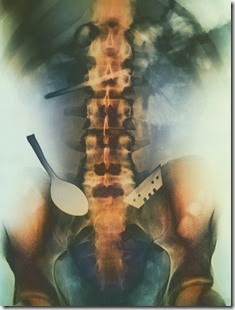

cassete

Bagaimana benda ini bisa masuk ke sana???